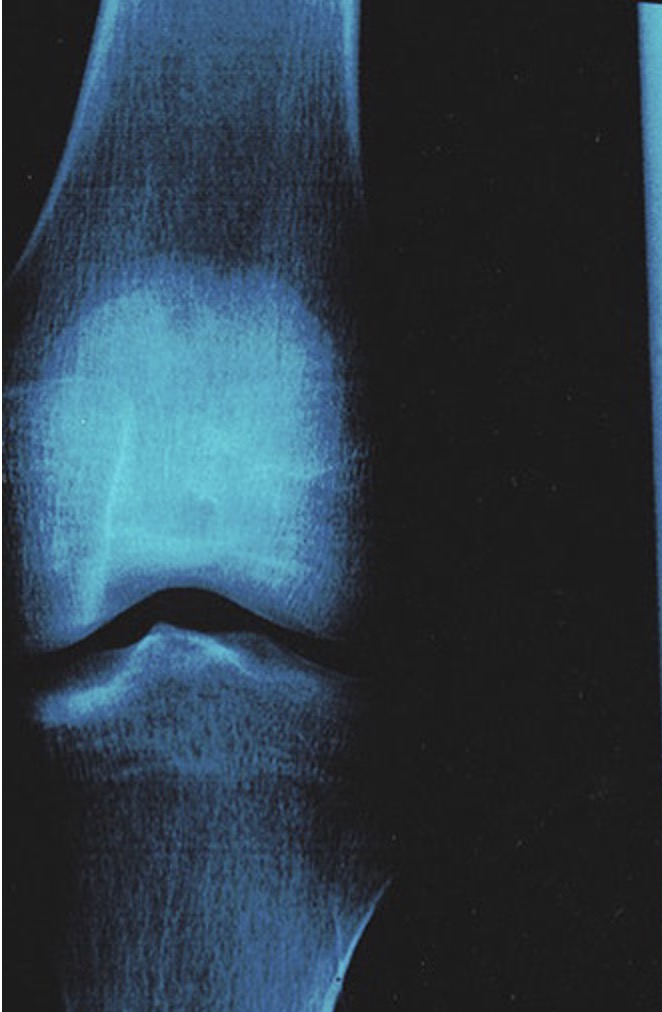

- 大多数膝关节问题是由损伤(扭伤或交叉韧带断裂)或退行性疾病(骨关节炎)引起的?你怎么看? 布骨康复医疗中心 ,2020-02-03

- 膝盖是一个由骨头、韧带、肌腱和软骨组成的系统,它使我们能够保持静止的姿势行走。它的机动性是基于滚动和滑动运动的结合。大多数膝关节问题是由损伤(扭伤或交叉韧带断裂)或退行性疾病(骨关节炎)引起的。 膝盖是一个很大的关节,它对支撑身体和保证身体的灵活性很重要。它由三块骨头组成:髌骨、股骨和胫骨、两个关.....